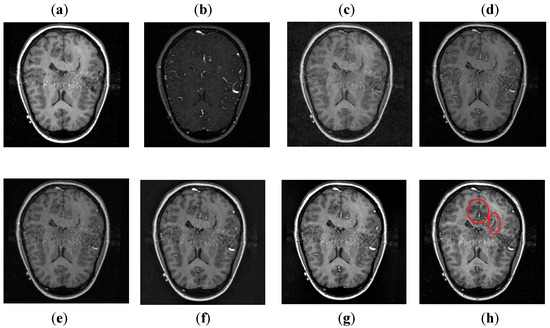

It can be depicted in Figure 8 that the DCT method contains most of the information from the CT image, but it fails to obtain more information from the MRI image. The DWT and NSST-SF-PCNN produce images with good contrast, but both methods cannot obtain more information about edges. The CSR method has better results than DCT, DWT, and NSST-SF-PCNN by producing less noise and good contrast images. However, this method also fails to capture more information about soft tissues. The CNN scheme and proposed method produce better results with uniform illumination, but it can be observed in red boxes that the proposed method can capture more information about edges and soft tissues and preserve whole useful information. Additionally, the proposed method effectively retains the complete information from both source images.

Figure 8. Data-2: (a) CT image, (b) MRI image, (c) DCT, (d) DWT, (e) NSST-SFT-PCNN, (f) CSR, (g) CNN, and (h) Proposed.